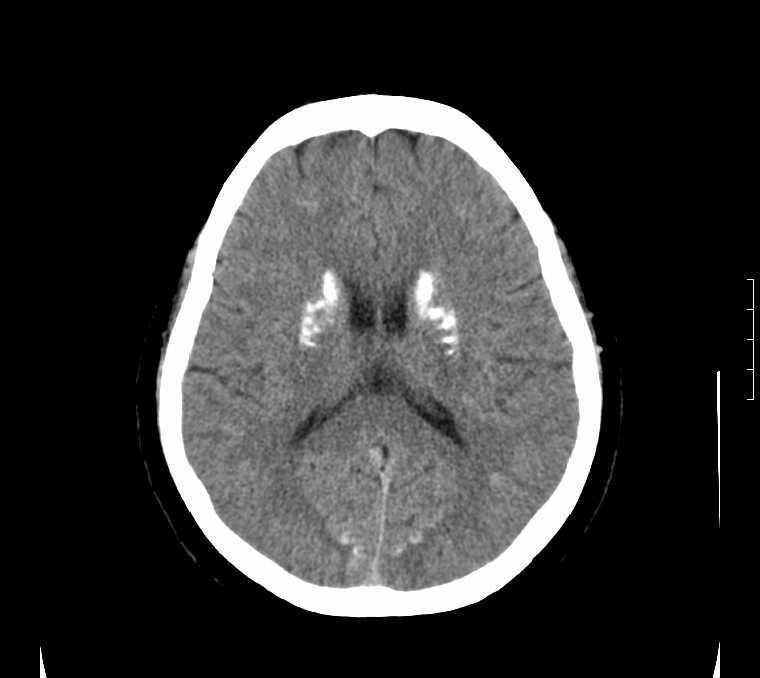

标题: CT24387:看看这例脑部改变!!

老年女性。头晕。

考虑:甲旁减。

fahr病

鉴别于特发性家族性脑血管亚铁钙沉着症(fahr`s病)与甲状旁腺机能低下之间,请结合临床及相关实验室检查。